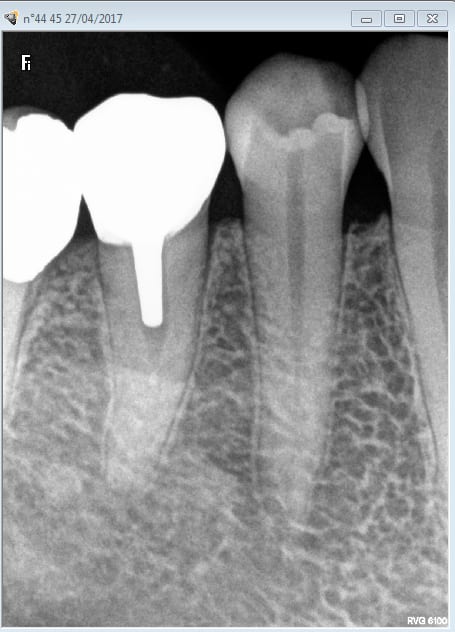

Alleeeez je peux pas résister. Nouveau patient bilan radio + endo 46 ( pas mal pour un premier RDV de 30 minutes). Bon j'avoue j'ai débordé de 10 mn.

Tiens casa a fait l'endo de 36 ? Pas de couronne dessus c'est tout à ton honneur. -)